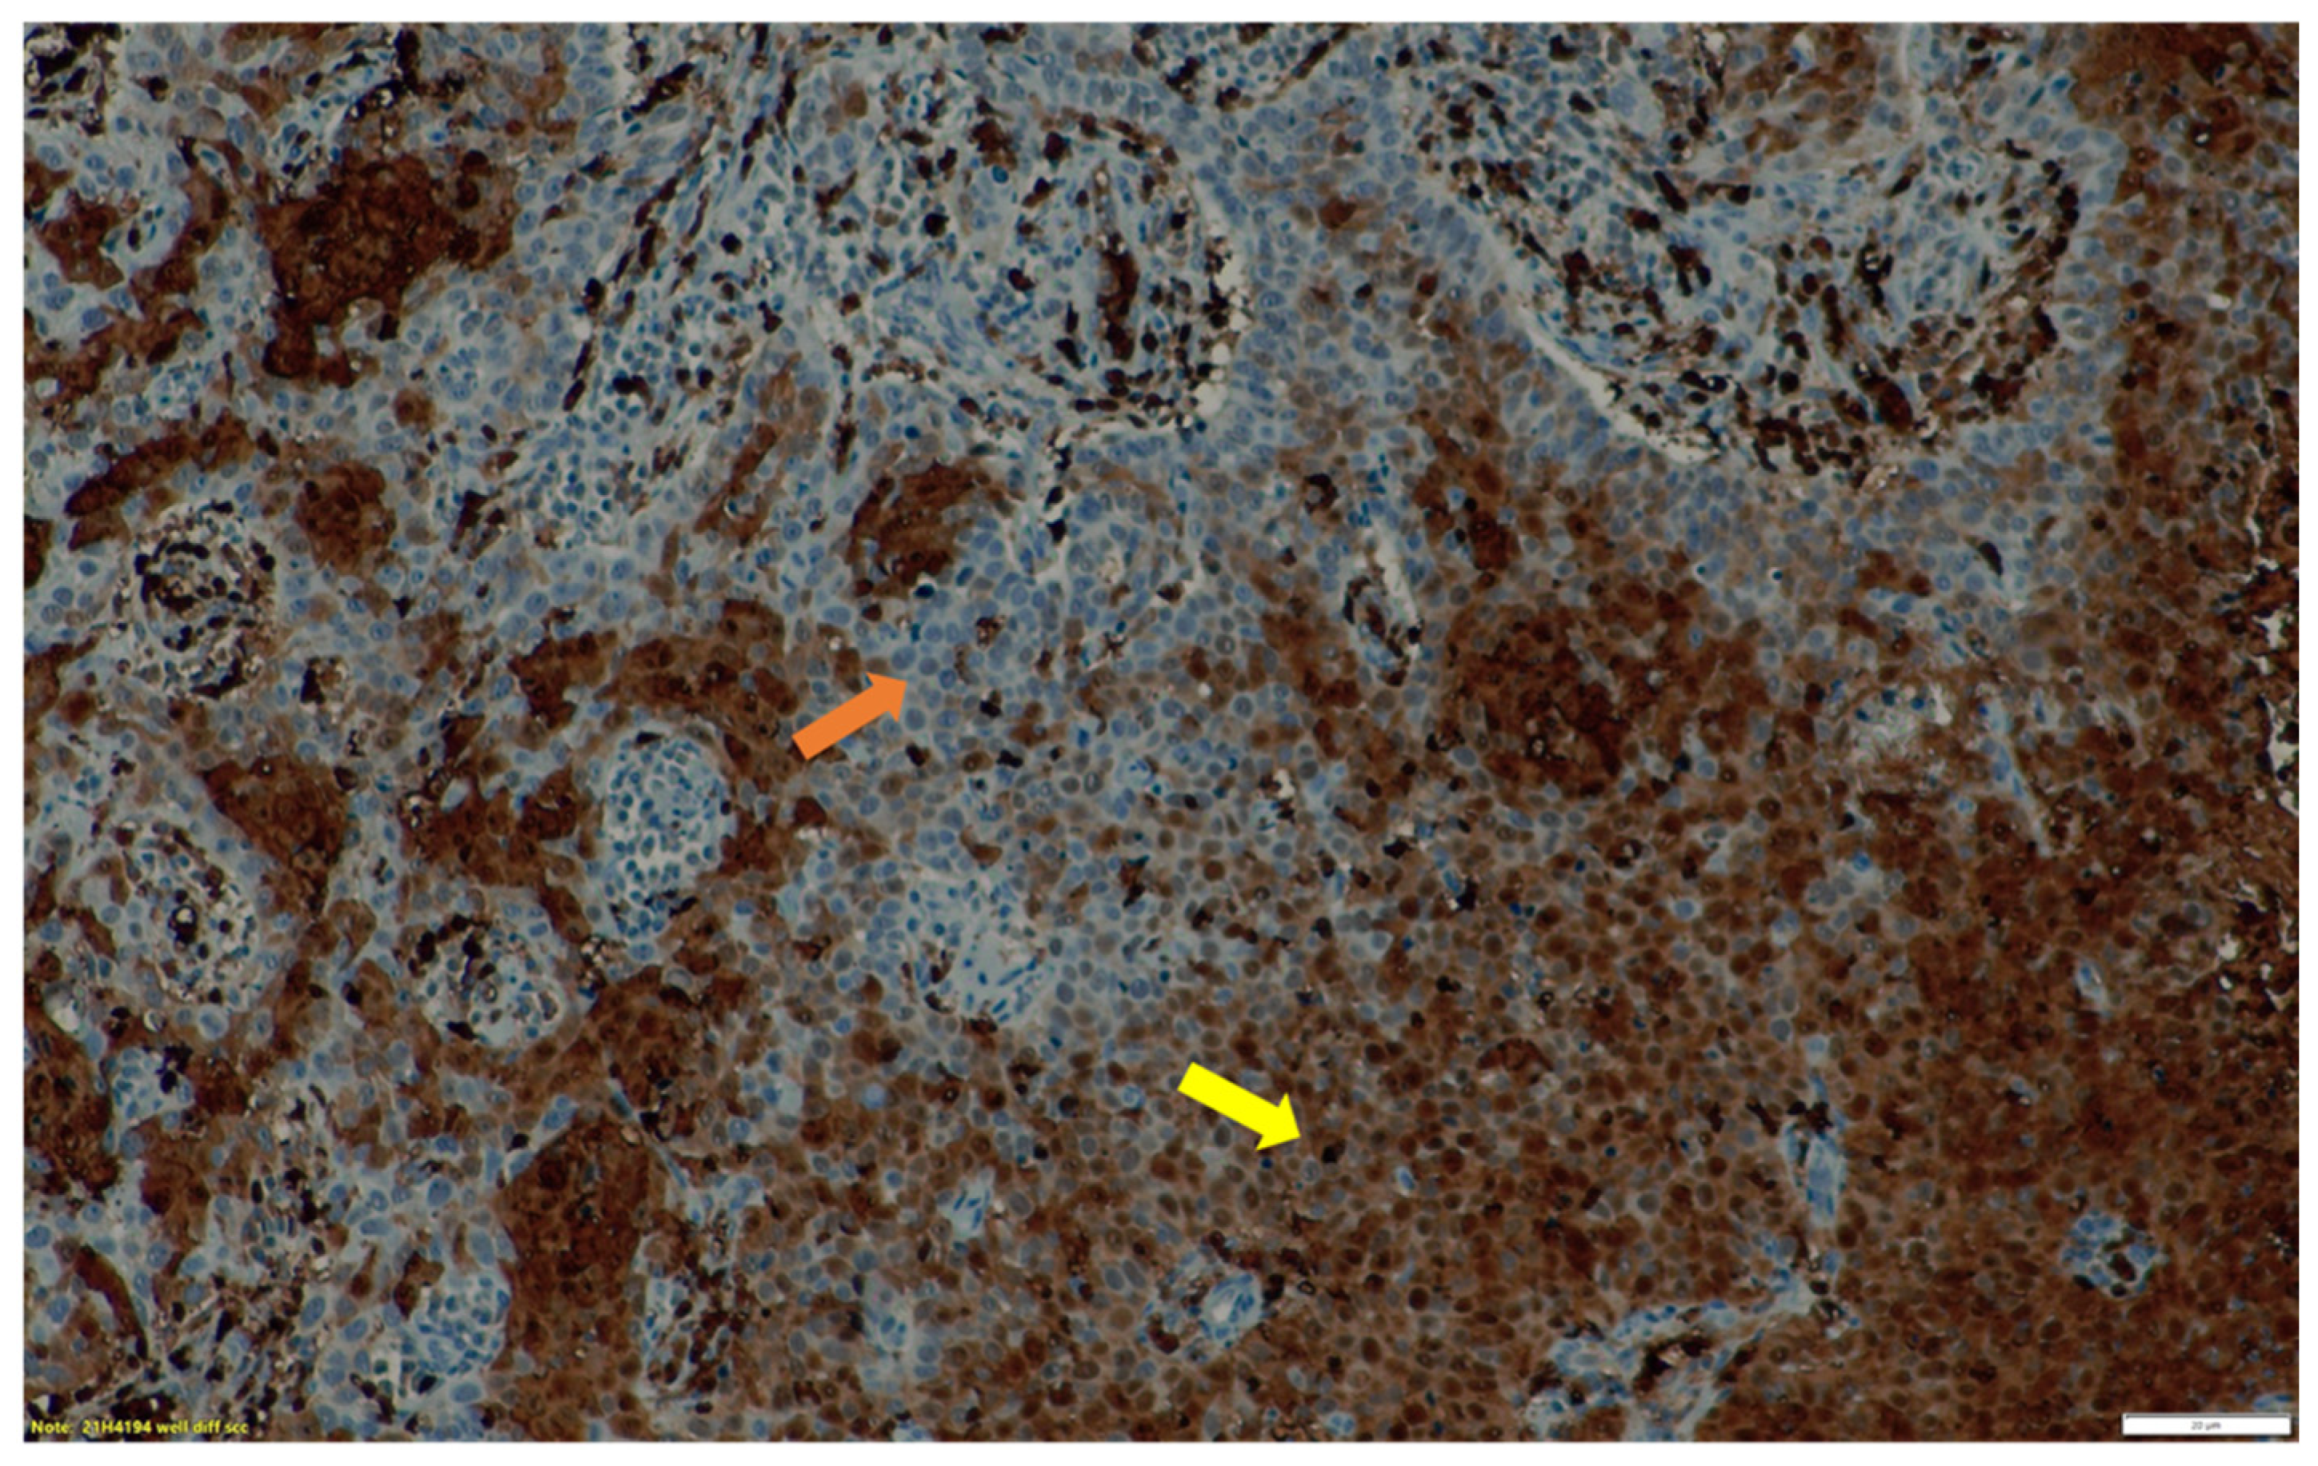

3.2. Immunohistochemistry Findings